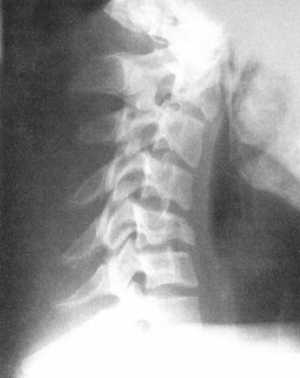

Рис. 3.6. Компрессионный перелом тела

С5 позвонка до и после операции. Стабилизация металлической конструкцией. |